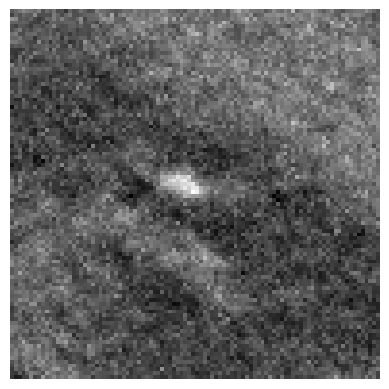

Refer to caption

(a)

(b)

(c)

(d)

Figure 3: Representation of generated features by DINO-LG model trained with label-guided approach and standard DINO training. Figure (a)𝑎(a)( italic_a ) represents a CT slice having calcified area and (b)𝑏(b)( italic_b ) shows annotated area for calcification. Figure (c)𝑐(c)( italic_c ) and (d)𝑑(d)( italic_d ) represent visualization of overlay self-attention maps are generated by standard DINO model and DINO-LG model, respectively.

Label-guided augmentation is effective for the data with only labels or prompt points. During the training phase, CT slices with annotations or labels are randomly augmented regardless of whether they have labels. In addition to this random augmentation, it is applied an augmentation which centers the center of annotated areas chosen randomly from labels. This point specific augmentation helps the model to emphasize on that labeled areas more than other randomly chosen and cropped areas. The point specific data augmentation or label-guided data augmentation has been applied for local data augmentations rather than global data augmentation, as the areas we want to highlight in features generated by DINO contain more localized information. The Fig. 2 represents locally guided data augmentation on a CT slice which includes a calcification. In our experiments, random local data augmentation was set to 8888, while guided local data augmentation was set to 6666, in order to preserve the randomness of the local data augmentation process. To illustrate the contributions of guided data augmentation, Fig. 3 presents a visualization of the outputs from the self-attention heads of DINO models trained using both label-guided and standard methods.